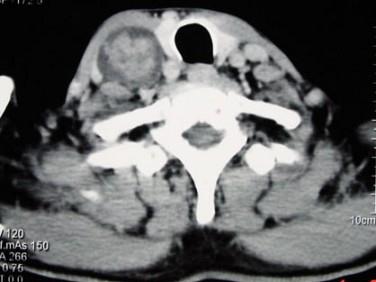

问题 男性,70岁,右侧颈部无痛性肿块3个月,CT扫描如图所示,请选择正确的描述和答案 ( )

选项 A、考虑迷走神经源性肿瘤 B、考虑交感神经源性肿瘤 C、右侧颈静脉被推压至肿块外后方 D、右侧颈动脉被推压至肿块内后方 E、右颈动脉间隙内见类圆形软组织肿块影,密度欠均匀,边缘光整

答案 ACDE